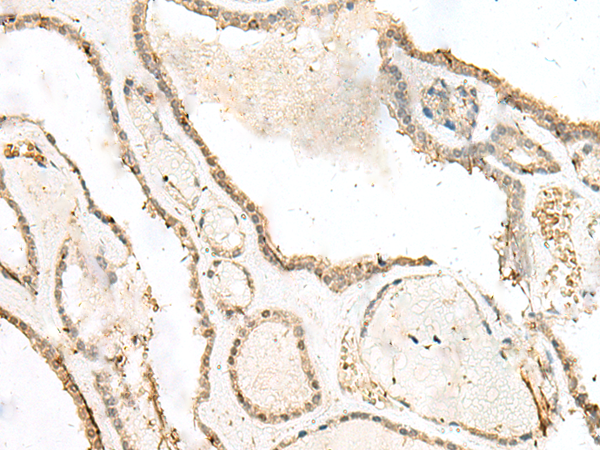

分类: 科研抗体货号: P09962别名:应用: IHC反应种属: Human, Mouse